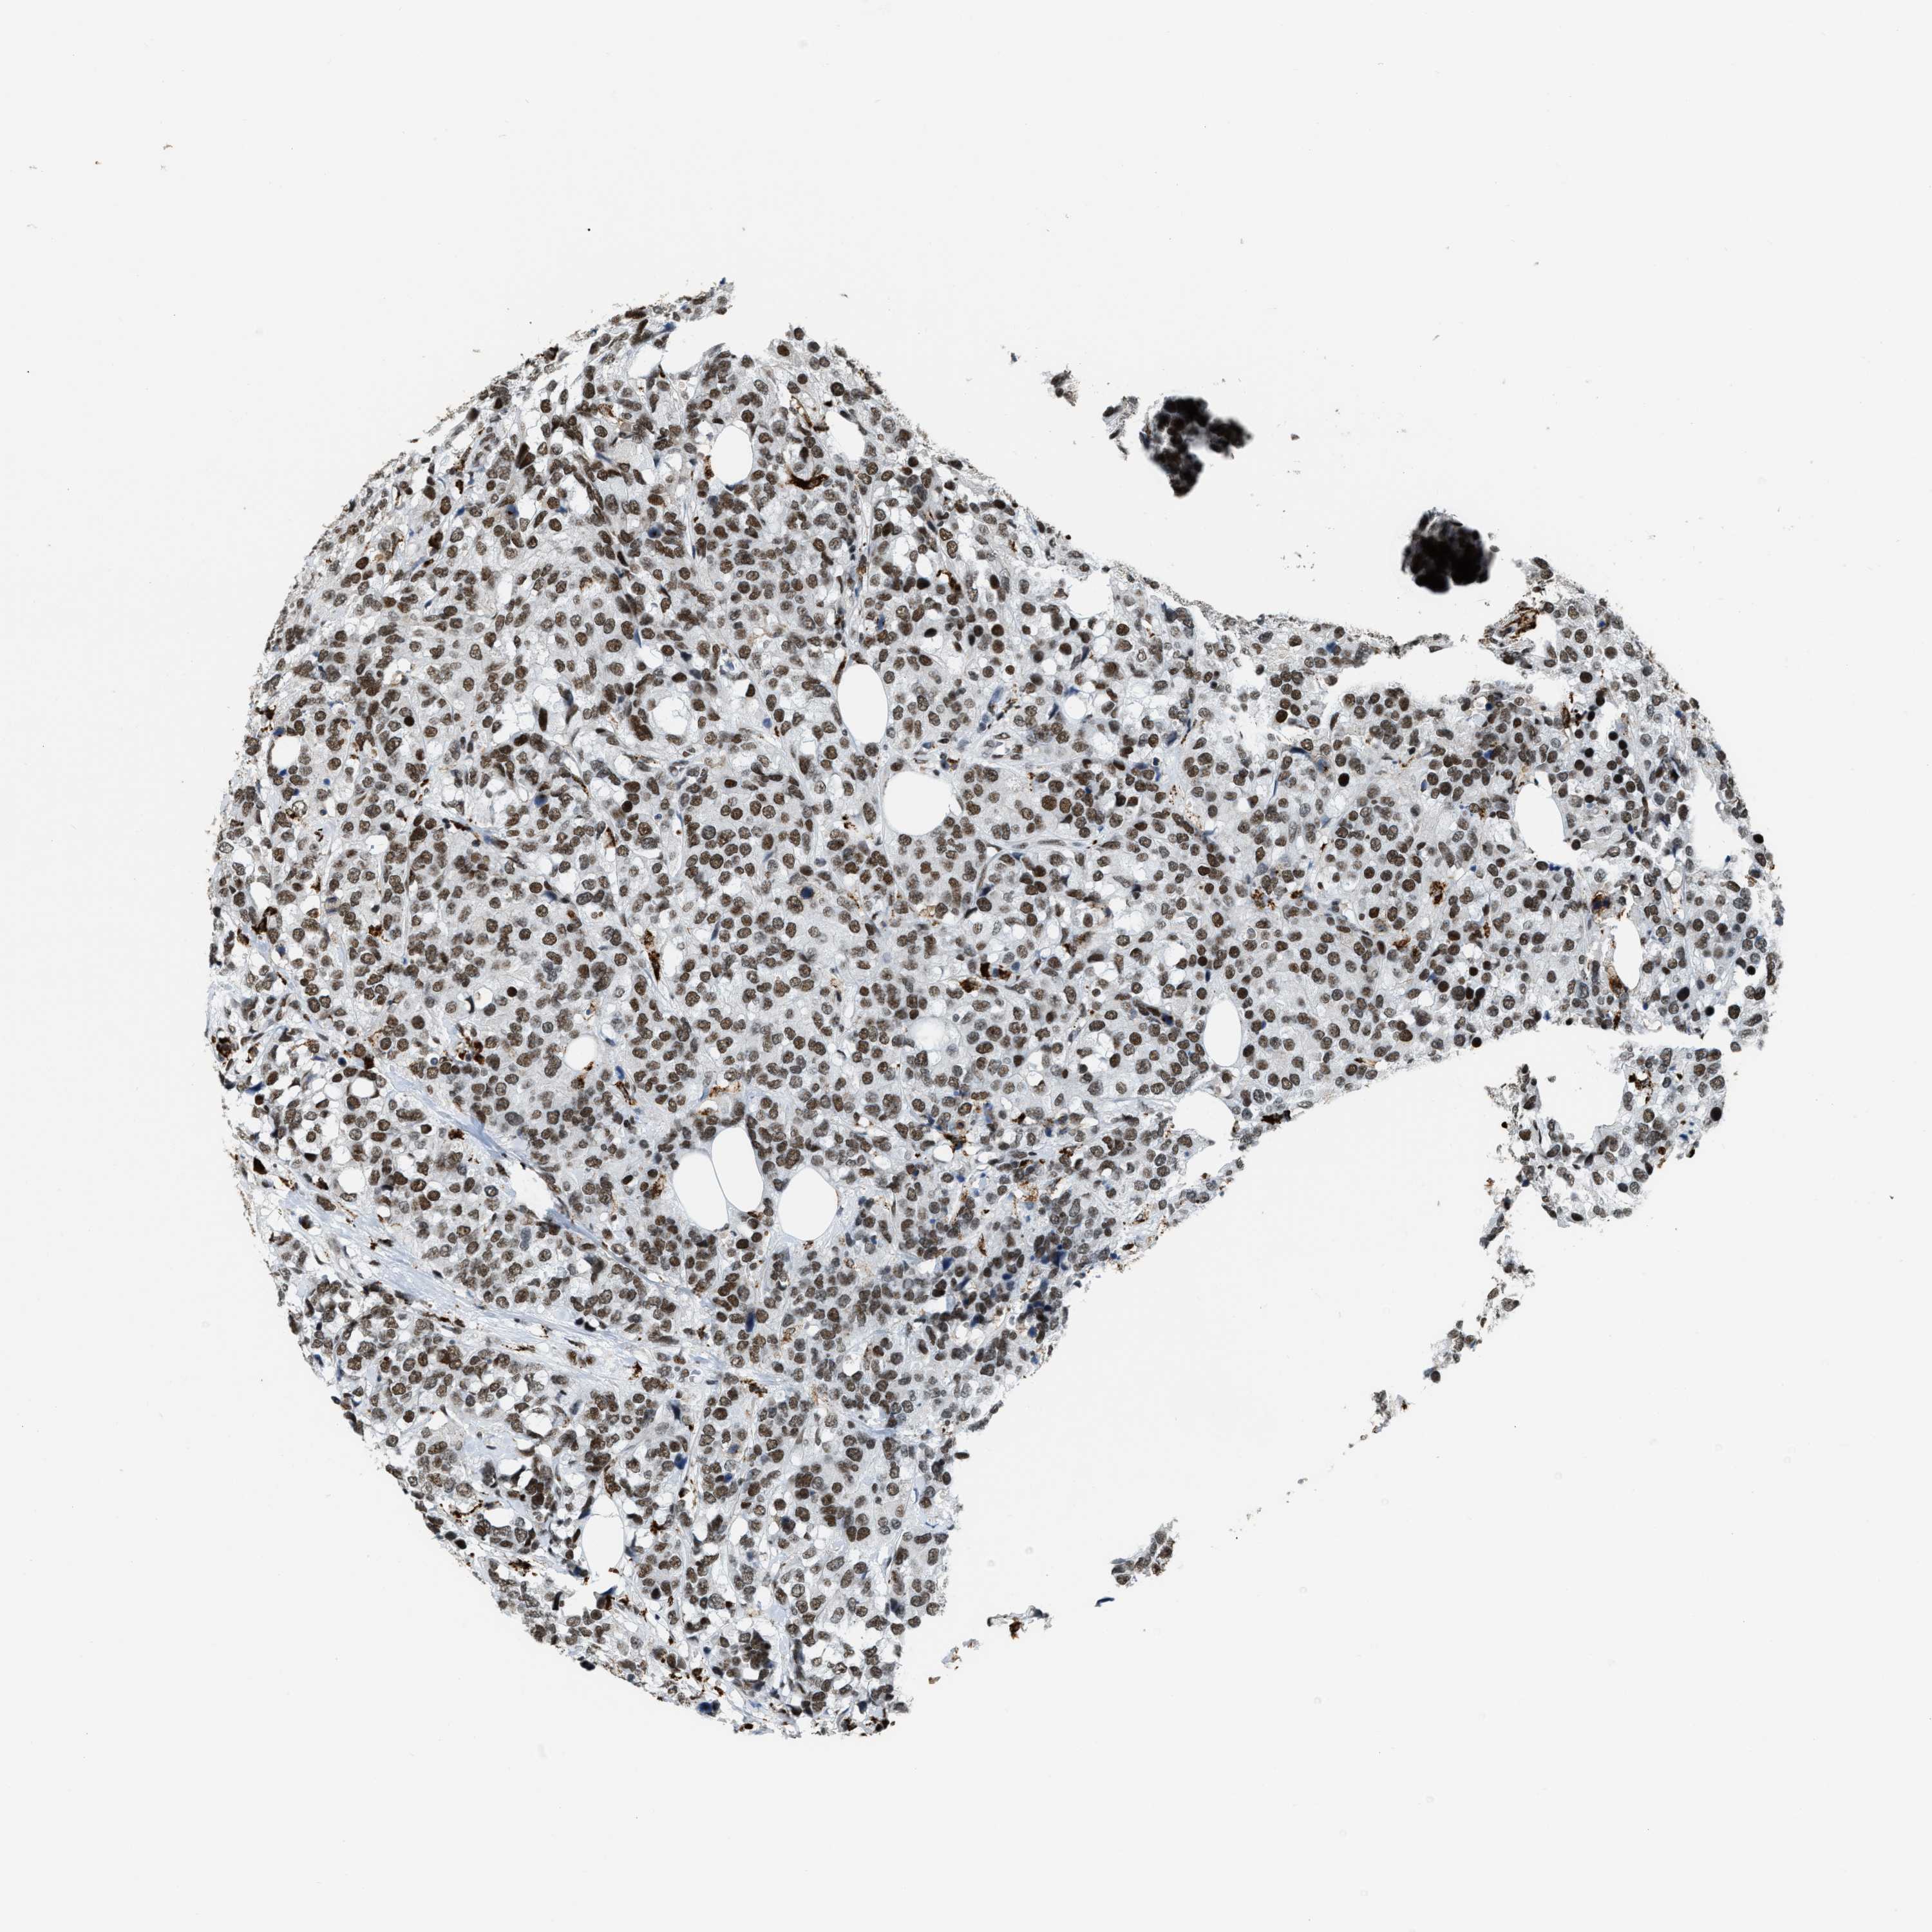

CANCER BREAST CANCER Show tissue menu

BRCA TCGA BRCA VALIDATION PROTEIN EXPRESSION